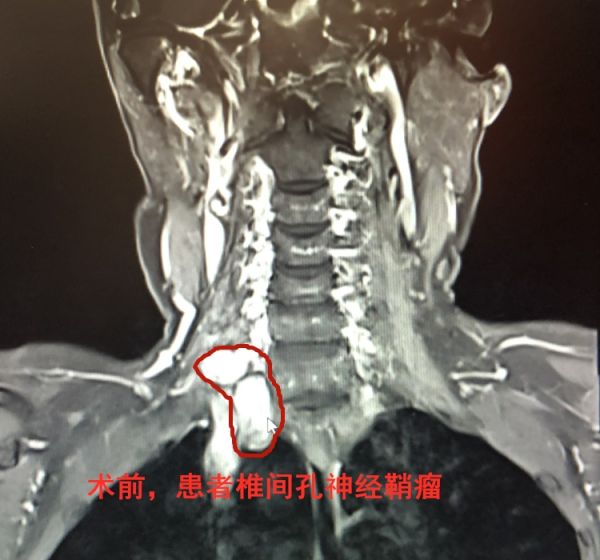

考虑张婆婆神经受压症状比较明显,为阻止病情加重产生致残风险,岑波建议她立即住院接受肿瘤切除手术。好在致病因被及时锁定,经充分的术前准备,岑波带领手术医师金盼盼、尹都,经过近6个小时的精细谨慎操作,在保证周边正常组织、神经血管完好的基础上,成功剥离并全切了肿瘤。术后一周,老人手臂的疼痛感消失,麻木感明显缓解,未出现上肢运动障碍,即将康复出院。术后病理结果证实,这块惹祸的肿瘤是椎间孔神经鞘瘤。

神经鞘瘤是颈椎管内最常见的肿瘤,因其症状与颈椎病造成的脊髓和神经根压迫原理类似,造成两者症状几乎一样,加之瘤体多为良性病变,进展相对缓慢,因此常易被误认为单纯颈椎病而延误治疗。岑波表示,神经鞘瘤早期发现、早期治疗很重要。一旦日常出现进行性加重的肢体放射性疼痛、运动障碍、感觉异常,在颈椎病常规治疗无效的情况下,建议及时到医院神经专科进行全面检查,以及早排除神经鞘瘤的可能。